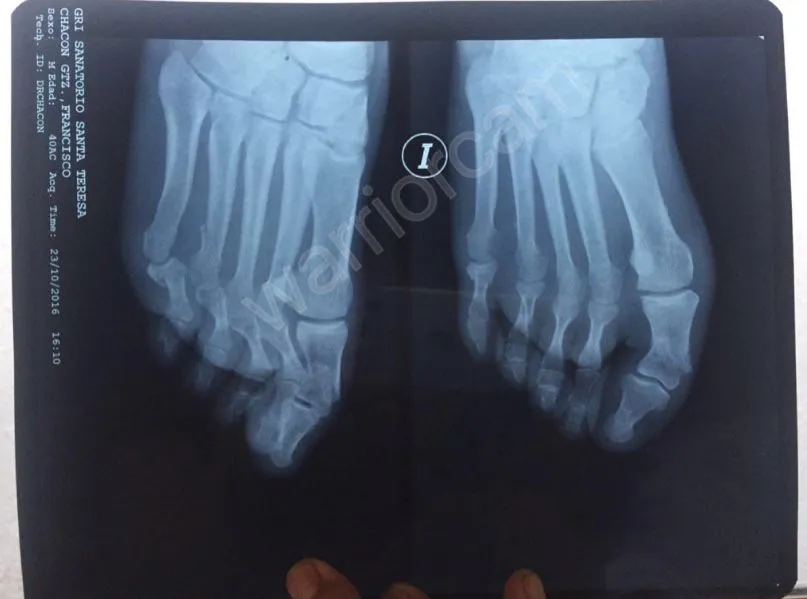

Francisco Chacón, árbitro de la Liga Mx, será baja por tres meses después de tener cuatro fracturas en tres dedos del pie mientras se encontraba en el gimnasio, por lo que se perderá lo que resta del Apertura 2016.

Después del percance, Chacón fue intervenido por el doctor Rafael Ortega, afamado cirujano del futbol mexicano. En la intervención le colocaron tres tornillos y dos placas para solucionar sus fracturas.